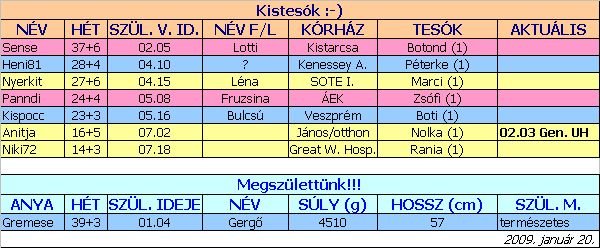

Mivel holnap zűrös napunk lesz, még ma dobok egy táblát holnapi adatokkal

Biztos ami biztos...

2008. május 13.

2008. május 13.  2008. május 16.

2008. május 16.  2008. május 19. 6+4

2008. május 19. 6+4